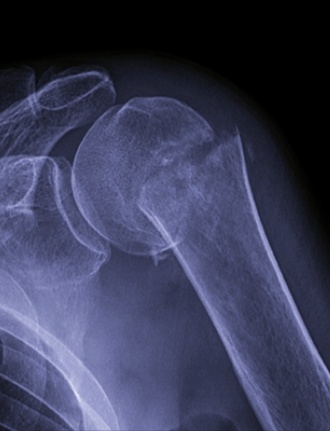

Пришла женщина, 73 года , на снимок плечевого сустава.Рука в косынке.

-Тогда так и вставайте,-разрешила я, явно перелом.

-2